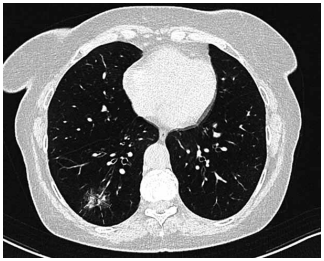

Mulher de 72 anos é atendida em consulta de retorno. O

histórico é positivo para tabagismo de 25 anos-maço e

DPOC (grau 3; grupo B). Recentemente, ela teve pneumonia com infiltrado persistente no lobo inferior direito

observado na radiografia de tórax. A paciente foi tratada

com antibiótico. Seu peso permaneceu estável, e ela não

apresentou febre ou sudorese noturna. Após seis semanas, uma radiografia de tórax de acompanhamento não

apresentou alterações. Uma tomografia é então realizada

e mostrada a seguir (a parte sólida do nódulo é de 7 mm):

(Arquivo pessoal; imagem usada com autorização)